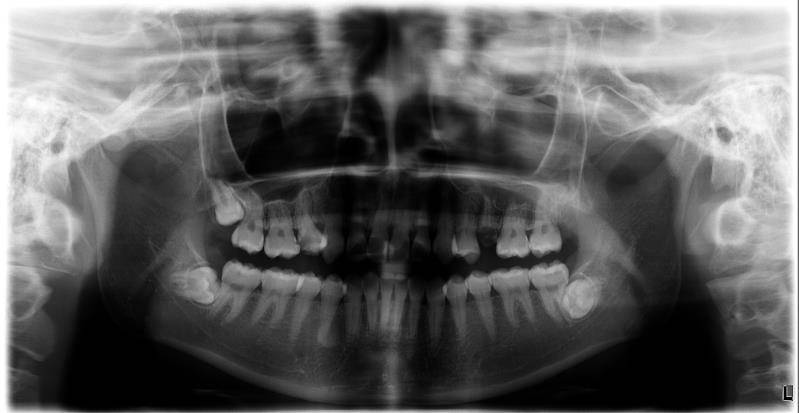

我补牙差已经补完了,目前没看到有,在这里我建议大家第一次初诊,拍个牙片,洗牙,洗牙是医生评估,觉得有牙结石,就去把牙齿洗干净(这里的洗牙不是把牙齿洗白,白到发光那种,因为牙齿本来就是淡黄色,才是健康的,)不要追求美白去做烤瓷牙贴边,这样是磨损了自己的好牙。以后后悔的。把牙齿的牙结石洗出来了,更看的清楚你的蛀牙面积,洗牙收费是根据牙结石严重程度收费,随后选择抛光,喷砂。我今天刚洗了,我看帖子,看到一些人说洗牙很多血,很痛苦,一直害怕去,今天鼓起勇气去,其实。还好,牙齿不是很脏,洗起来不错。洗完觉得牙齿附着的牙菌斑都没了,还有一些垢。收费150里面内含抛光了洗完以后觉得发酸发软,是正常了,过几天就好了。发现牙缝大了,那是医生把结石清出去,这是你正常的牙缝。不是故意这样。期间别吃硬的东西,可以刷牙用抗敏感牙膏。

智齿是牙齿的8号牙,随着人类的进化,有些人存在智齿,有些人很幸运没有。智齿如果长歪,顶着隔壁正常的大牙,半萌生状态容易发炎,这种是是没有用的,得经过医生评估拔除。如果复杂类型的,得拍ct片评估具体位置。智齿的拔除是根据难度,和机器决定,太难的那种,得用超声骨刀。这是附加费。